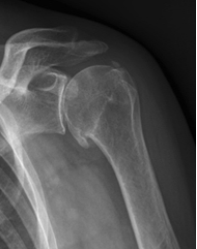

Artrose wordt ge­ken­­merkt door kraak­been­verlies.

Dit kraak­been­verlies kan ook worden veroorzaakt door eer­dere be­scha­diging (trauma) van de schouder of door ziekten zoals reuma. De schouder wordt in de loop der jaren langzaam stijf en pijnlijk.

Dit merkt u doordat simpele dagelijkse handelingen, zoals iets uit een kast pakken, aankleden of  wassen moeilijker worden.

Diagnose en onderzoek

Bij het lichamelijk onderzoek vinden we meestal een bewegingsbeperking die pijnlijk is. Verder zal een röntgenfoto de diagnose bevestigen. Een MRI of CT, voorafgaande aan een operatie, kan nuttig zijn om de vorm van de kom beter te beoordelen en de kwaliteit van de omringende spieren (rotator cuff).